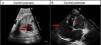

Caso 1Paciente de 18 meses con sospecha prenatal de dilatación aneurismática de la orejuela derecha de 4cm2 de área en plano de 4 cámaras a la 31,6 semanas de edad gestacional (SEG) sin otros antecedentes familiares de interés. Se realizó cesárea electiva a las 39SEG ingresándose para monitorización. No presentó incidencias durante el parto ni en periodo perinatal. Se inició tratamiento con ácido acetil salicílico (AAS) manteniéndolo actualmente por persistencia de dilatación significativa. El tamaño de la orejuela ha ido disminuyendo, teniendo un área de 8cm2 con 4 meses de vida y de 5cm2 en el último control ecocardiográfico con 18 meses, sin objetivarse trombos en su interior y con cuerpo de la aurícula derecha normal (fig. 1). No se han detectado arritmias en los electrocardiogramas seriados ni ha presentado otras complicaciones, permaneciendo asintomática y con exploración física normal en todo momento.

Caso 1. Dilatación de orejuela derecha. A) Ecocardiografía fetal a las 31 semanas de edad gestacional en la que se señala la dilatación de orejuela derecha. B) Ecocardiografía: último control postnatal a los 18 meses de edad con dilatación de orejuela derecha de 5cm2 (flecha).AD: aurícula derecha; AI: aurícula izquierda; VD: ventrículo derecho; VI: ventrículo izquierdo.